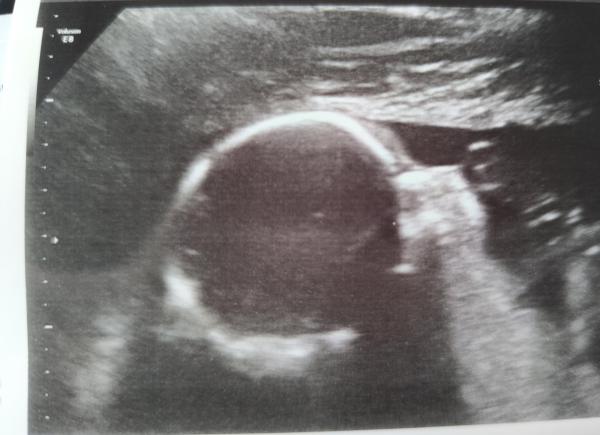

Wir hatten heute unseren Screeningtermin. Das Baby ist total aktiv und liegt in Querlage. Mit dem Gesicht so stark in die Plazenta gekuschelt, dass wir leider die Naern- und Lippenpartie nicht richtig sehen konnten, dementsprechend gibt es auch kein "Modelbild". Die Trikuspidalklappe konnte man leider aufgrund der Lage ebenfalls nicht richtig beurteilen, die war beim ETS noch undicht. Das wird in 4 Wochen nochmal geschaut.  Insgesamt war alles toll entwickelt! Und es war richtig schön so lange nach dem Baby schauen zu können.    Er ist auch wirklich ein Junge, ich bin total froh nun auch ein Bild gesehen zu haben und nicht nur den Nipt.   Meine Arterien zeigen Wiederstände mit Notching bzw angedeutetem Notching, für 21+0 SSW ist das aber im Rahmen.   Er wiegt ca 380 Gramm, im Moment habe ich bei mehrmaligem Testen eigentlich immer Spuren von Eiweiß, meistens + Eiweiß im Urin, aber der Blutdruck ist nach Absetzen von Cariban gesunken.    Ich drücke euch die Daumen für eure Ultraschalle   Liebe Grüße

Huhu 🙂 Ziemlich ruhig hier bei uns geworden... Es freut mich, dass dein 2. großes Screening insgesamt positiv war und die Klappe wird in 4 Wochen bestimmt auch dicht sein. 🍀 Und auch die Bilder sind schön geworden, auch wenn es kein richtiges Profilbild gab. Smiley nr152.gif Ich kann nachempfinden, dass es doch nochmal was anderes ist, wenn man das Geschlecht dann auch selber im Ultraschall erkennt. Das war bei uns auch so, erst dann kann man es "so richtig glauben". Seit wir die Ergebnisse aus dem NIPT wissen, wurde auch bei jedem Ultraschall nochmal gezeigt, dass es wirklich ein Mädchen ist. 😁 Wir hatten diese Woche die zweite Feindiagnostik. Es war so schön, der Ultraschall ging über eine halbe Stunde und wir konnten so viel von ihr sehen. 🩷 An sich ist im großen und ganzen alles in Ordnung, allerdings sind ein paar Sachen aufgefallen, die mich verunsichern. Zum einen ist sie bereits 620g schwer bei einer Größe von 28cm. Das ist deutlich zu viel für die Woche. Innerhalb von 3 Wochen hat sie damit ihr Gewicht verdoppelt obwohl sie "nur" 4cm gewachsen ist. Angeblich habe ich auch deutlich zu viel Fruchtwasser, was somit beides Indizien für Schwangerschaftsdiabetes sind. Den hatten wir ja aber eigentlich schon vor Wochen ausgeschlossen. Dann kommt dazu, dass ich so gerne per 3D einen genauen Blick auf ihre Nasen- und Lippenpartie bekommen hätte. Es wurde allerdings nur ein einziges Bild gemacht und da hatte sie ihre Hände genau davor. Es wurde lediglich in 2D nach der Lippe geschaut, dass da alles okay ist, aber für mich als Laie hat da leider das deutlich Visuelle als Bestätigung gefehlt.  Ansonsten ist aber wirklich alles positiv gewesen, alle Fingerchen dran usw. Ihre Füße haben 4,2cm gemessen, ihr Ohr 2,1cm und der Kopfumfang liegt schon bei 22cm. Das Herz sah top aus ebenso wie das Gehirn und die anderen Organe. Viele Werte waren wieder überdurchschnittlich, teilweise auf der 98. Perzentile und überwiegend der 25. Woche entsprechend. Nach dem Fruchtwasser habe ich dann später nochmal recherchiert, dass die Messwerte eigentlich vollkommen in der Norm waren/sind. Bin gespannt, was meine Gyn nächste Woche dazu sagen wird. Beunruhigt bin ich trotzdem, da unsere Wunsch-Klinik nicht bei SS-Diabetes entbinden kann und abgesehen davon, birgt zu viel Fruchtwasser ja auch Risiken. 🤔 Tritte merken wir nach wie vor deutlich auch von außen. Sie ist aktuell in BEL und das merke ich leider oft an meiner Blase - ihre Füße liegen genau darüber. 🫣 Ich hoffe, es geht allen gut. Lasst mal wieder was von euch hören. Liebe Grüße Susuba, 22+1